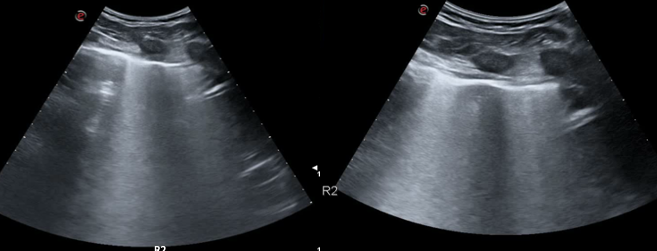

A 30-year-old man presents to the emergency department (ED) due to syncope. For the last 10 days he had had fever, cough and dyspnea. At the ED his peripheral oxygen saturation was 86%, BP 130/80, HR 88bpm, RR 20 /min and his temperature 37.4°C. He was given oxygen via a mask. Chest CT was performed and later lung ultrasound (LUS) was performed in 12 areas longitudinal/oblique views using a convex array probe followed by a linear array probe for details (figure 1).

On imaging, initial lesions are usually peripheral because SARS-COV-2 attacks the small distal airways. Several reports have described the findings in chest CT. Most commonly few, small, segmental ground glass opacities are seen peripherally and basal. These may deteriorate to become bilateral and multisegmental and finally consolidation and/or ARDS. Most common LUS signs are: vertical pleurogenic artifacts with varying degree of intensity (from few to confluent). These alternate with clear demarcation to A-lines in the same area, especially in the mid- and upper lung. Pleural thickening, sometimes marked, due to the presence of numerous, small subpleural consolidations. Lobar or translobar consolidations of large size and minimal pleural effusions. The LUS features match with the site and kind on CT.

LUS is an examination, which can be carried out bedside. It may provide early information of presence of diffuse multifocal pneumonia (as in COVID-19) and its deterioration (enlarging consolidations). By doing LUS in cases with COVID-19 pneumonia, transport of patients through the hospital and unnecessary exposure of staff and other patients is avoided. Similar LUS signs as the ones described have been observed in other kinds of viral epidemic pneumonia. If they, individually or in combination, have some specificity for COVID-19 pneumonia it should be established with further appropriate studies.